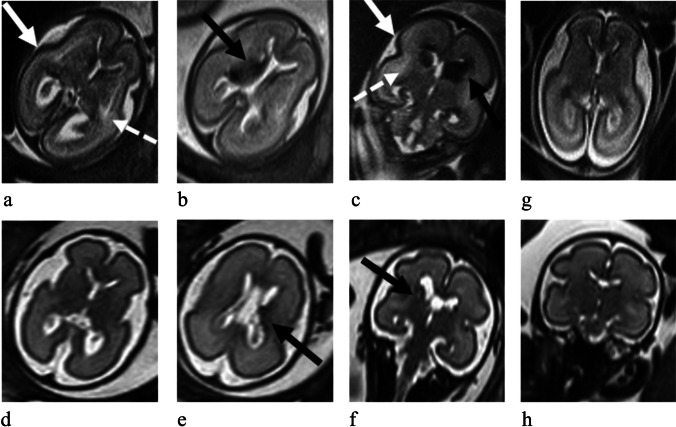

Twin Anemia-Polycythemia Sequence (TAPS) intracranial Magnetic Resonance (MRI) main findings in six different exemplificative cases: a) axial ss-FSE T2-weighted image from 24 week study showing bilateral intraventricular haemorrhage—IVH (black arrows), b) axial ss-FSE T2-weighted section from 22 week study showing bilateral para-trigonal blurred areas of higher T2-weighted signal (black arrow-heads), c) axial ss-FSE T2-weighted section from 25 week study showing cortical liquoral space obliteration due to brain swelling (arrow), d) coronal ss-FSE T2-weighted sequence from 22 week study showing germinal matrix hematoma (black arrow) with periventricular radial T2-weighted hypointensities (white arrow-head), brain swelling (white arrows), e–f) coronal and sagittal ss-FSE T2-weighted sections from 22 and 21 week study showing prominence of transverse and sagittal sinuses (arrow-heads in case in e), and deep medullary vein system (arrow-heads in case in f)

Following TAPS diagnosis through US, among 12/55 fetuses with abnormal intracranial MRI findings (21.8%), nine were anemic and three polycythemic. Most of the twins showed more than one anomaly.

Hemorrhagic lesions, with different characteristics, in five subjects (8.8%). In particular, we detected three (ID04, ID08 and ID11) unilateral linear T2-weighted hypointensities along the ventricle margin (low grade germinal hemorrhage), two (ID05, ID07) bilateral hematomas within the germinal matrix (higher grade hemorrhage), and two (ID05, ID07) periventricular radial T2-weighted hypointensities (as small hemorrhages in the deep medullary veins territory), one was unilateral and one bilateral. Altogether, these findings were present in three anemic and in two polycythemic fetuses.

T2-weighted periventricular white matter hyperintense areas (WMHs) in four patients (ID01, ID03, ID07 and ID12) (7%). This finding is suggestive of periventricular areas of parenchymal vasogenic-interstitial edema. This pattern was recognized only in the anemic fetuses.

Diffuse generalized brain swelling in six patients (ID01, ID03, ID05, ID07, ID10 and ID12) (10.5%). This entity consists of parenchymal enlargement with consequent obliteration of the periencephalic CSF spaces in fetuses with normal skull biometry. Also, this finding was detected only in anemic fetuses.

Prominence of dural sinuses and deep medullary veins in 7 patients (ID01, ID07, ID09, ID10, ID12 and ID13) (12.3%). Venous prominence was recognizable as unequivocable marked dilation of the dural sinuses and/or prominence of the deep medullary veins, recognizable as periventricular radially oriented venous structures. Venous findings were detected in 6 anemic fetuses and only in one polycythemic.

Unilateral ventriculomegaly: unilateral, found in one polycythemic patient (ID11) (1.8%).

All findings are summarized in Table 3 divided between anemic and polycythemic twins. Given that most of the twins showed more than one type of anomaly, a total of 19 intracranial findings were present in the anemic twins and only three in the polycythemic ones, with a statistically significant ratio between the two groups (chi-square of 7.42; p-value = 0.01 and Fisher exact test of 0.01).